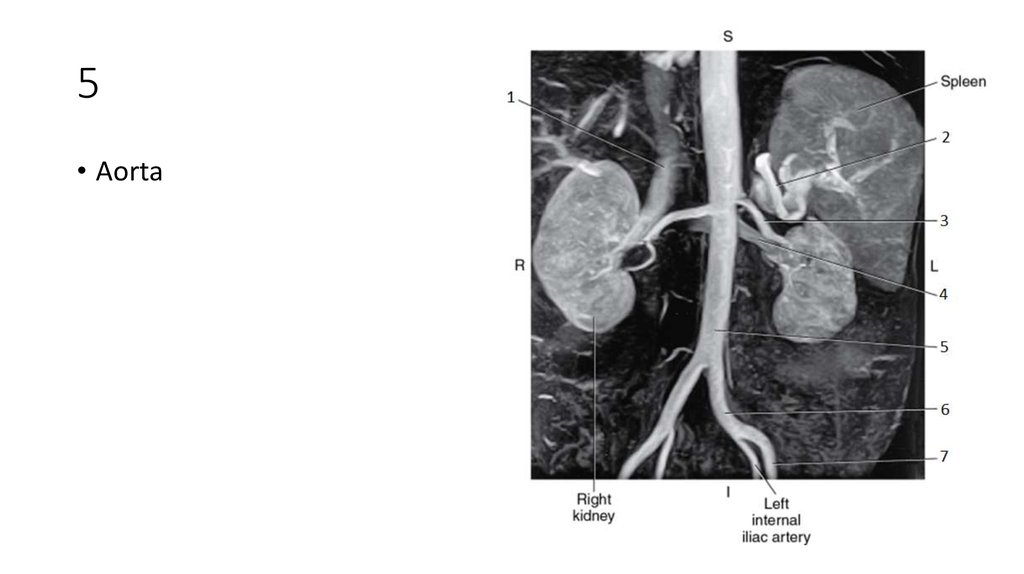

70. 5

71. 5

• Aorta